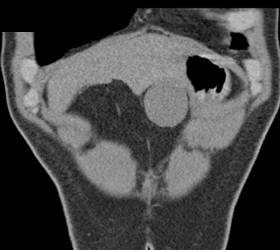

Partial Splenic Vein Occlusion Due to Portal Hypertension